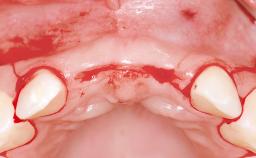

Bone Volume | Deficient horizontally, allowing simultaneous augumentation |